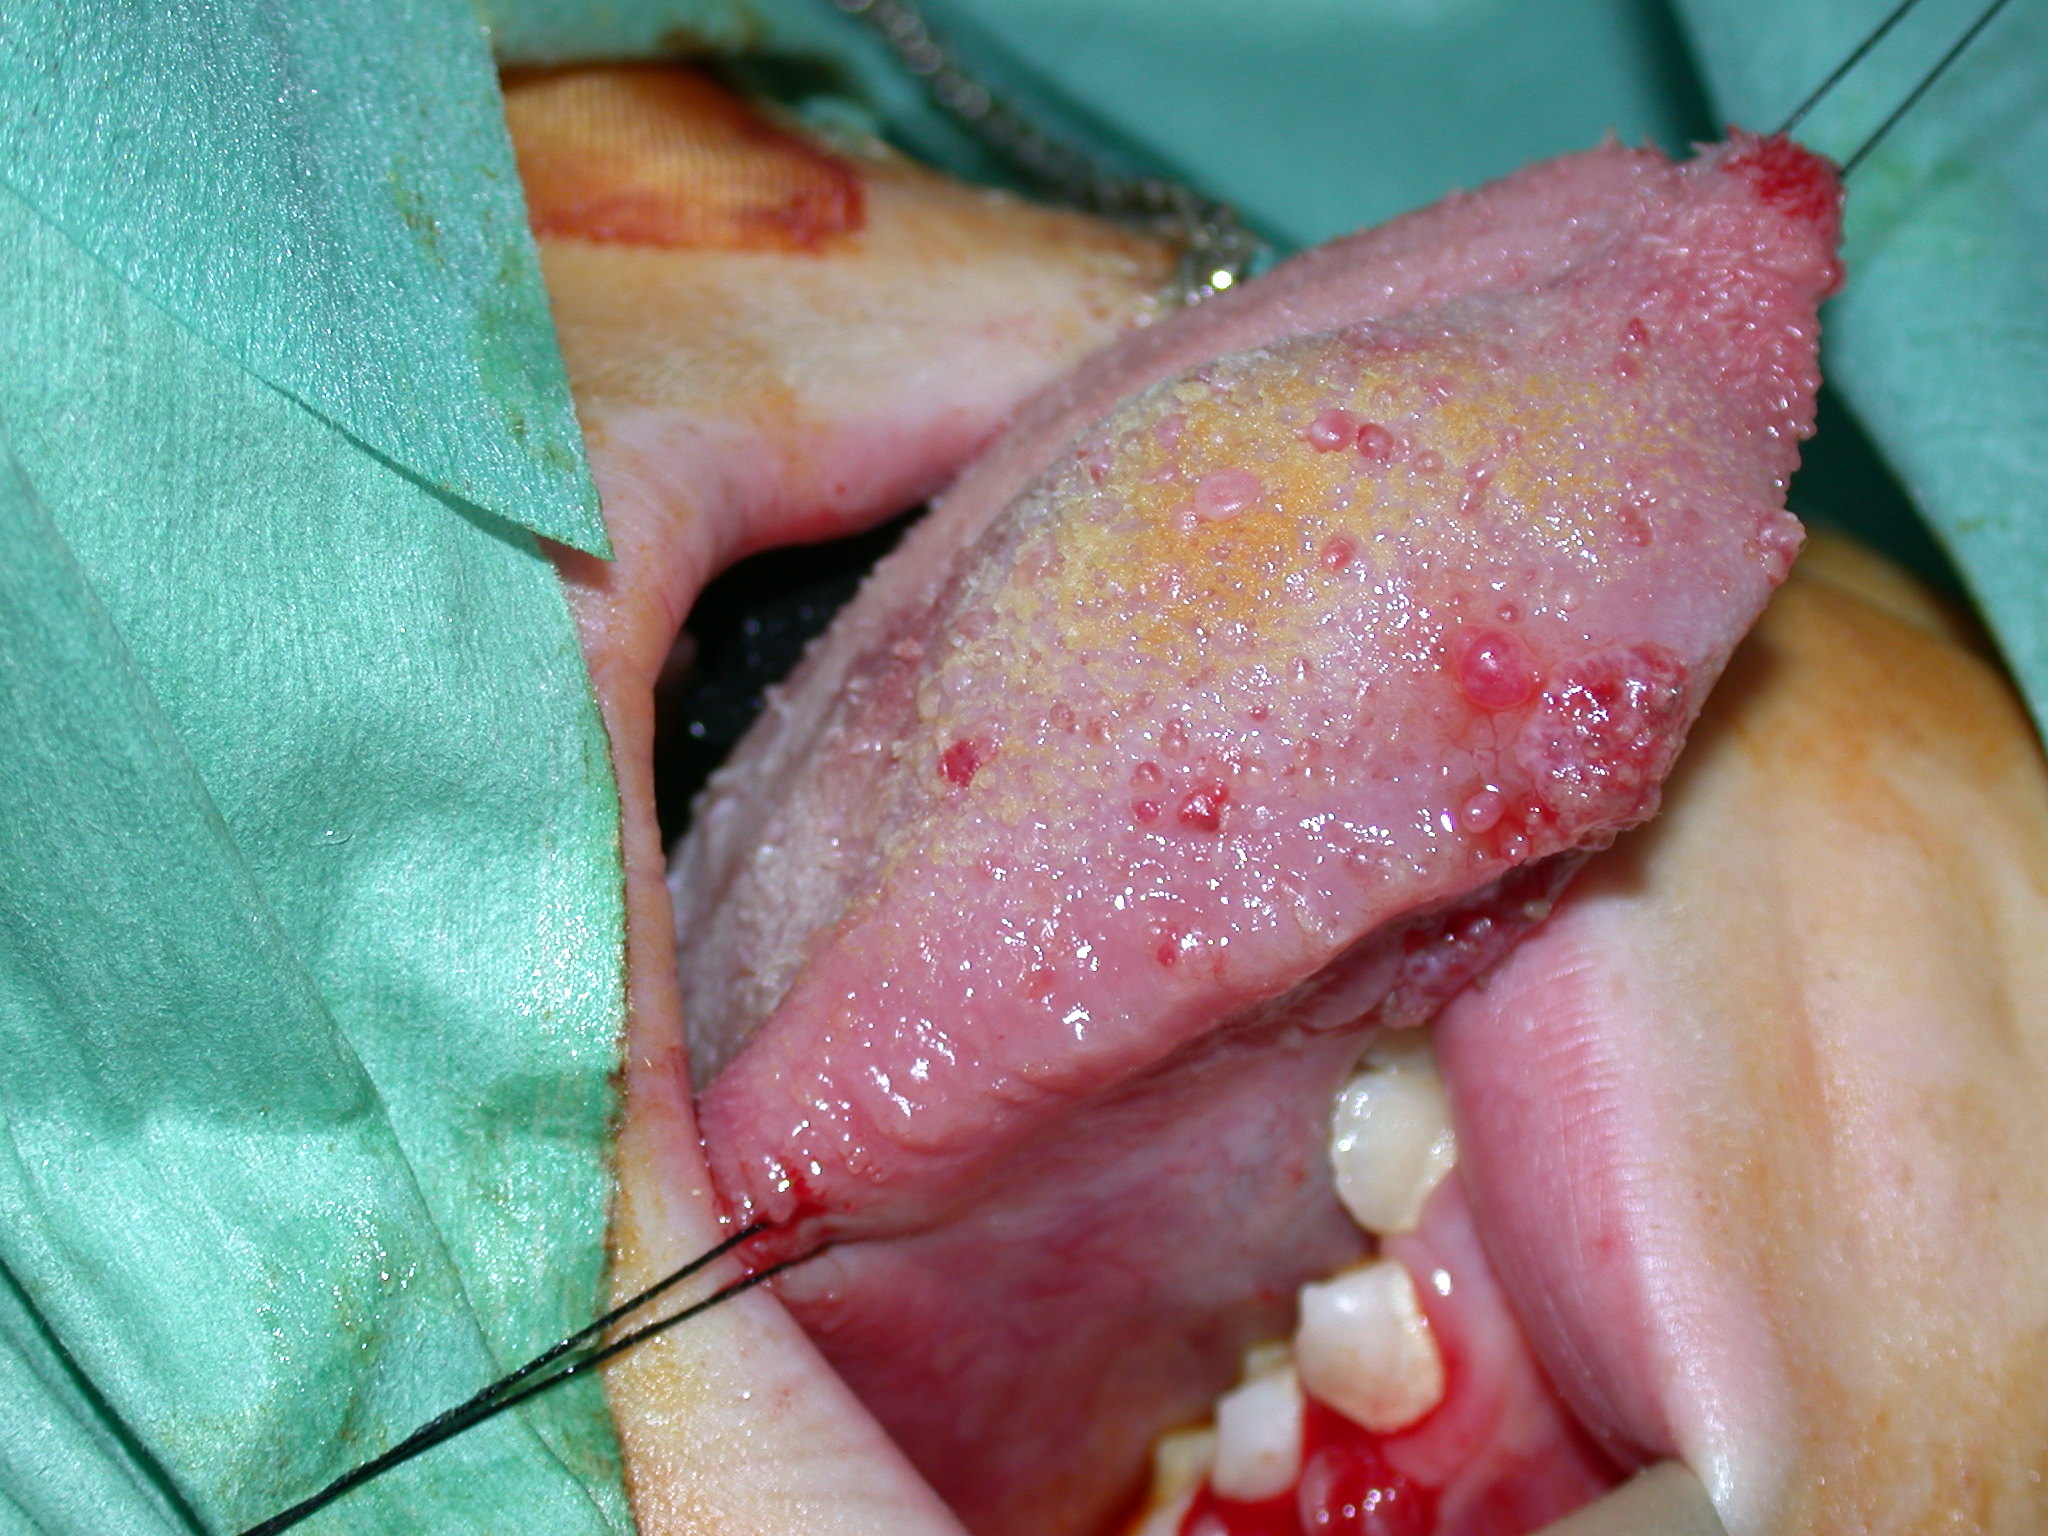

Lymphatic malformations are a genuine puzzle in many cases. These lesions present as macrocystic and microcystic malformations. Basically macrocystic lymphangiomata are big benign cysts and can be managed as such. Microcystic lesions are problematic in that they can vary in presentation in time and place in the same person. This can create a very confusing story and can sometimes mean the story of recurrent substantial swelling of an organ (for example the tongue) is doubted. The microcystic lymphatic lesion depicted in Figure 4 could at various times be invisible, or completely block the front of this girl’s mouth.

Figure 4: Microcystic lymphatic malformation of the tongue.